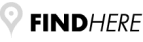

Χειρουργική laser σύγχρονων κυκλικών ινών:

- Θεραπεία αιμορροϊδων με laser (LHP)

Χειρουργική laser σύγχρονων κυκλικών ινών:

- Θεραπεία αιμορροϊδων με laser (LHP)